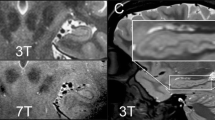

Kharatishvili I, Immonen R, Grohn O, Pitkänen A. Quantitative diffusion MRI of hippocampus as a surrogate marker for post-traumatic epileptogenesis. Brain 2007;130:3155–3168.

Immonen R, Kharatishvili I, Grohn O, Pitkanen A. MRI biomarkers for post-traumatic epileptogenesis. J Neurotrauma 2013;30:1305–1309.